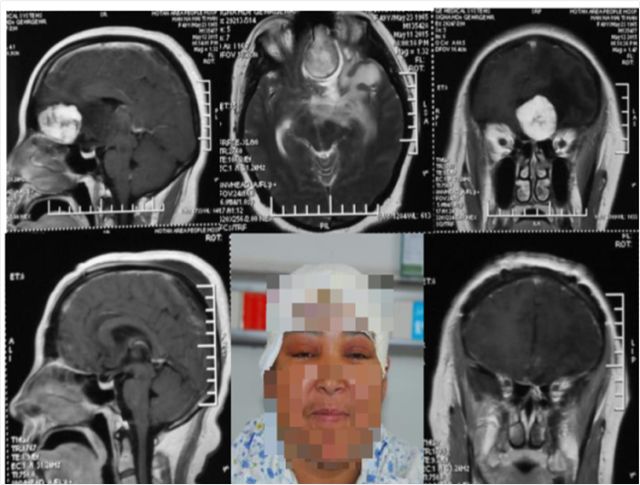

嗅沟脑膜瘤

岩斜脑膜瘤